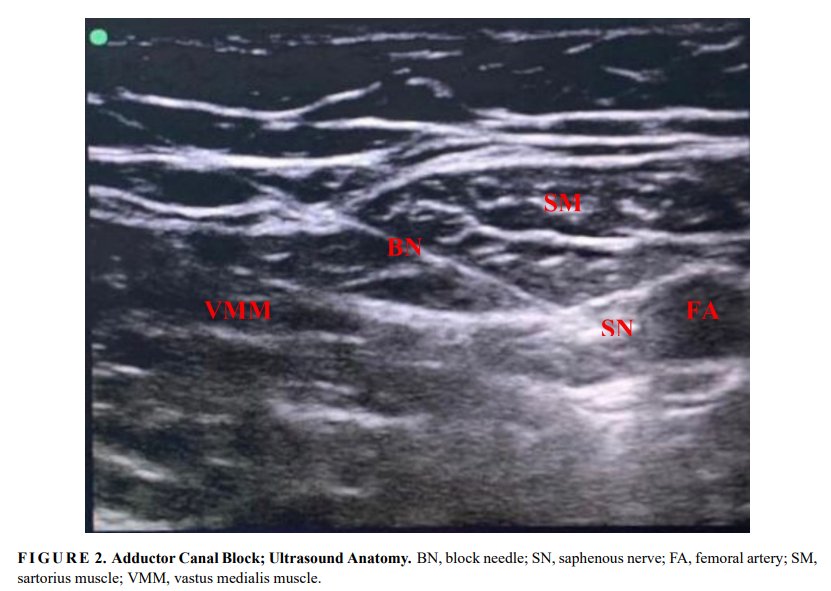

📷 【Article Title】 II International Conference “Medical Simulation-Practical Applications and Technologies” 📷【Click】 https://t.co/Nyuve1YTvM #Postoperativepainmanagement;#Peripheralnerveblock;#Kneearthroplasty;#Epiduralanalgesia;#Rehabilitation;#Rehabilitation;